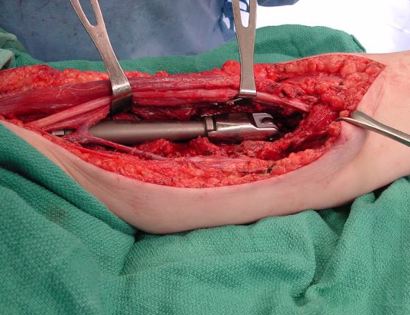

This is an image of the arm after the humerus bone is removed along with the tumor. The colored lines are to pull back and identifying major arteries and veins so that damage to these structures does not occur.